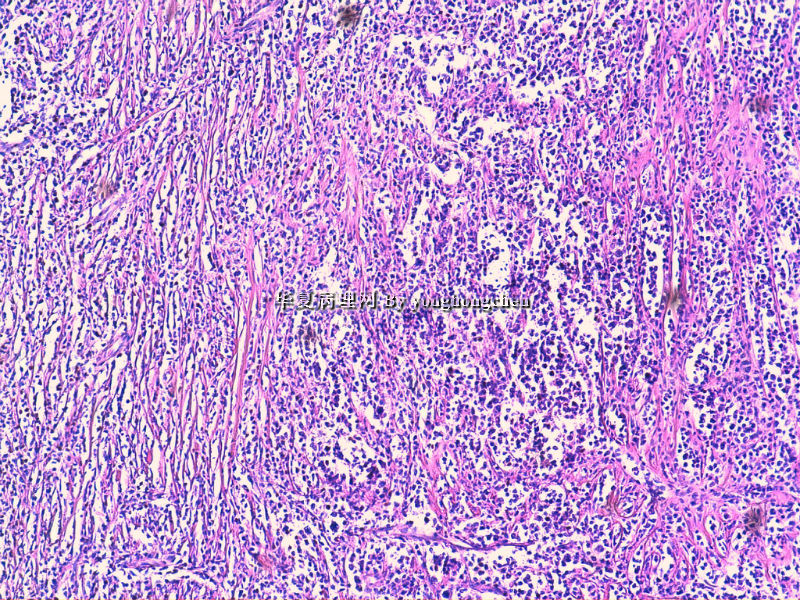

好的HE切片和准确可靠的免疫组化结果是淋巴瘤等较难病例病理诊断的基础。本例从HE来看不太像典型的淋巴瘤或癌,免疫组化就很重要了,但本例组化结果之间似乎不易解释:

1.syn与LCA等淋巴系标记的阳性判断,镜下须观察阳性细胞是否一致,是相同的细胞还是不同的细胞等

2.如果考虑淋巴瘤,B系的标记如CD20和PAX5结果也不太一致,另外CD133+究竟如何也有待探讨,好像楼主未显示其图片

3.ALK等也不太确切,

不知楼主以上的组化结果阴阳性对照如何?我个人经验不足,不敢妄下结论,但认为诊断淋巴瘤(弥漫大B,或间变淋巴瘤)可能会有风险。

今天又做了免疫组化,请大家帮看看。CD10(-),CD138(-),CDX2(-),CD3(-),CyclinD1(-),CD2(-),CD117(-),CD7(-),CD30(-),CD23(-);CD20强(+),BCL-2,Bcl-6,EMA,PAX-5,MUM-1,CD5,ALK,CD68都是散在阳性,大家帮确定一下是否阳性。B细胞淋巴瘤可以确定了,不知是哪种类型的?

是的,syn(+),LCA(+), CD79a阳性, CD3阴性,NSE是局部胞核,胞浆着色,主要是胞浆着色;SYN也是局部,主要是胞核着色,胞浆很少。不对吗?我也迷糊。也许我看错了,不像那种典型的胞浆颗粒状着色。大家帮看一看。